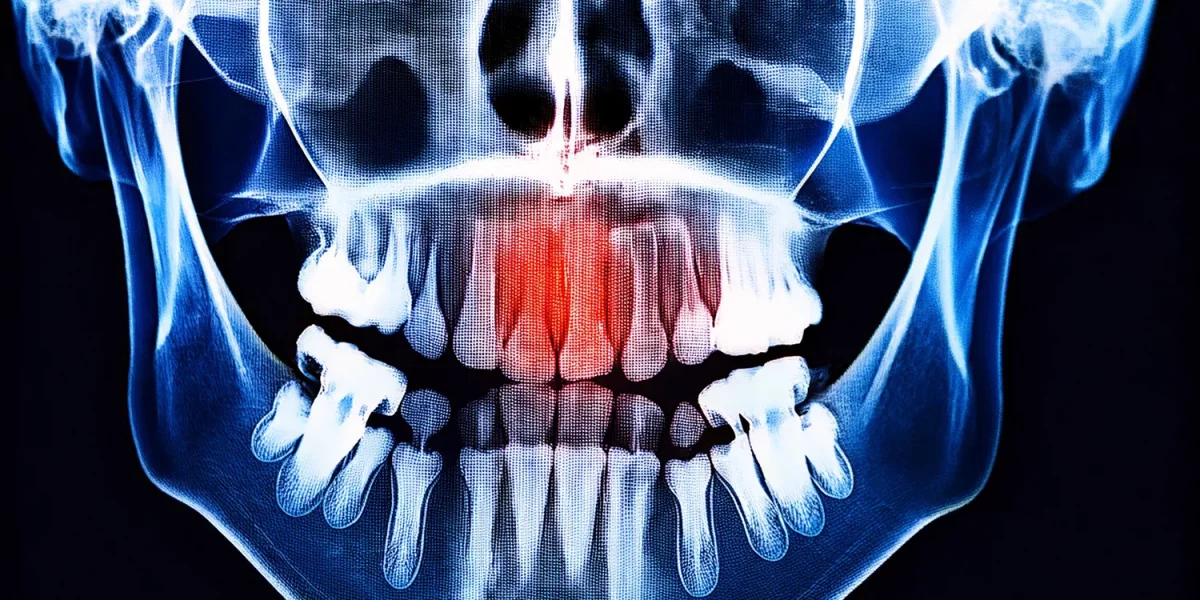

1. Panoramik Röntgende Görülen "Gölge" Nedir?

Öncelikle temel bir noktayı açıklayalım: Panoramik röntgen, diş hekimliğinde en çok kullanılan genel tarama röntgenidir ve ağız ile çeneleri tek bir görüntüde gösterir.

Bu filmde:

1. Yoğun, neredeyse beyaz görülen alanlar: Genellikle kemik, dolgular, metal veya implant benzeri yapılar.

2. Daha koyu, neredeyse siyah görülen alanlar: Kemik yoğunluğunun azaldığı veya "boş" alanlar, kistik/tümöral/normal boşluklar gibi bölgeler.

Bu nedenle raporda belirtilen terim:

"Radyolüsensi" veya "radyolüsan alan" basitçe "röntgende koyu görünümlü bir bölge" anlamına gelir.

Bu koyu alan bazen şunlar olabilir:

1. Sıradan anatomik bir boşluk (örneğin, sinüs boşluğu).

2. Normal bir varyasyon.

3. Bir dişten kaynaklanan çene kisti.

4. Daha nadiren, tümöral bir oluşum.

Yani, sadece "bir gölge var" ifadesi kanseriniz olduğu anlamına gelmez. Ancak bu, ciddiye alınması ve bir ağız ve çene cerrahı tarafından değerlendirilmesi gereken bir bulgudur.